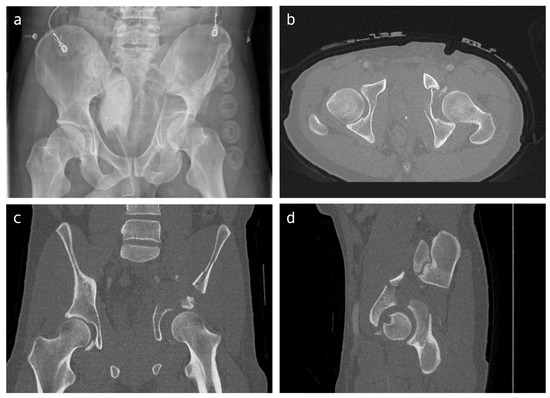

A ‘3D survey’ was generated to explore whether virtual 3D reconstructions of the fracture could influence the treatment strategy of both-column acetabular fractures. The same fifteen cases and case description information of the 2D survey were presented in this survey. Additionally, for each patient, the CT data (≤2 mm slices; spatial resolution, 0.5–0.6 mm) were transformed and used to create a 3D reconstruction using Mimics Medical software version 19.0 (Materialise, Leuven, Belgium) by an experienced technical physician (Figure 2). Semi-automatic segmentation of all fracture fragments was performed using a specific preset threshold for bone. Each fracture fragment was assigned a different color. The final 3D reconstructions were stereolithography (STL) files. These were exported to Filmbox (FBX) format and uploaded to Autodesk Viewer: a browser application that enables uploading, viewing, and sharing of 3D designs. It was possible to rotate the 3D model in all directions in this viewer. Surgeons were presented with the same information as in the 2D survey: age, gender, pelvic radiographs, and 2DCT images. However, in this 3D survey, a virtual 3D fracture reconstruction was presented in addition to the conventional imaging. Participating surgeons were asked the same questions as in the 2D survey: (1) elaborate on the preferred treatment strategy; (2) which surgical approach they would use to perform the surgery; and (3) the level of confidence in the chosen treatment strategy.

Figure 2. Virtual 3D reconstruction of a both-column acetabular fracture as provided within the surveys (surgeons could rotate and view the model in every direction). (Left): anterior view, (right): view into the acetabulum.